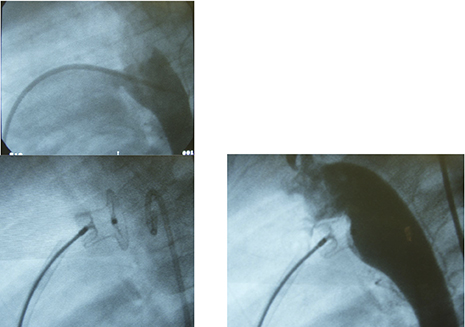

この渡航では、計3回にわたるカテ、トータル14個のコイルで何とか閉鎖できた径8mmのPDAを経験しました。その画像です。コイル閉鎖限界症例と今でも思っています。後に国際学会で報告しました。